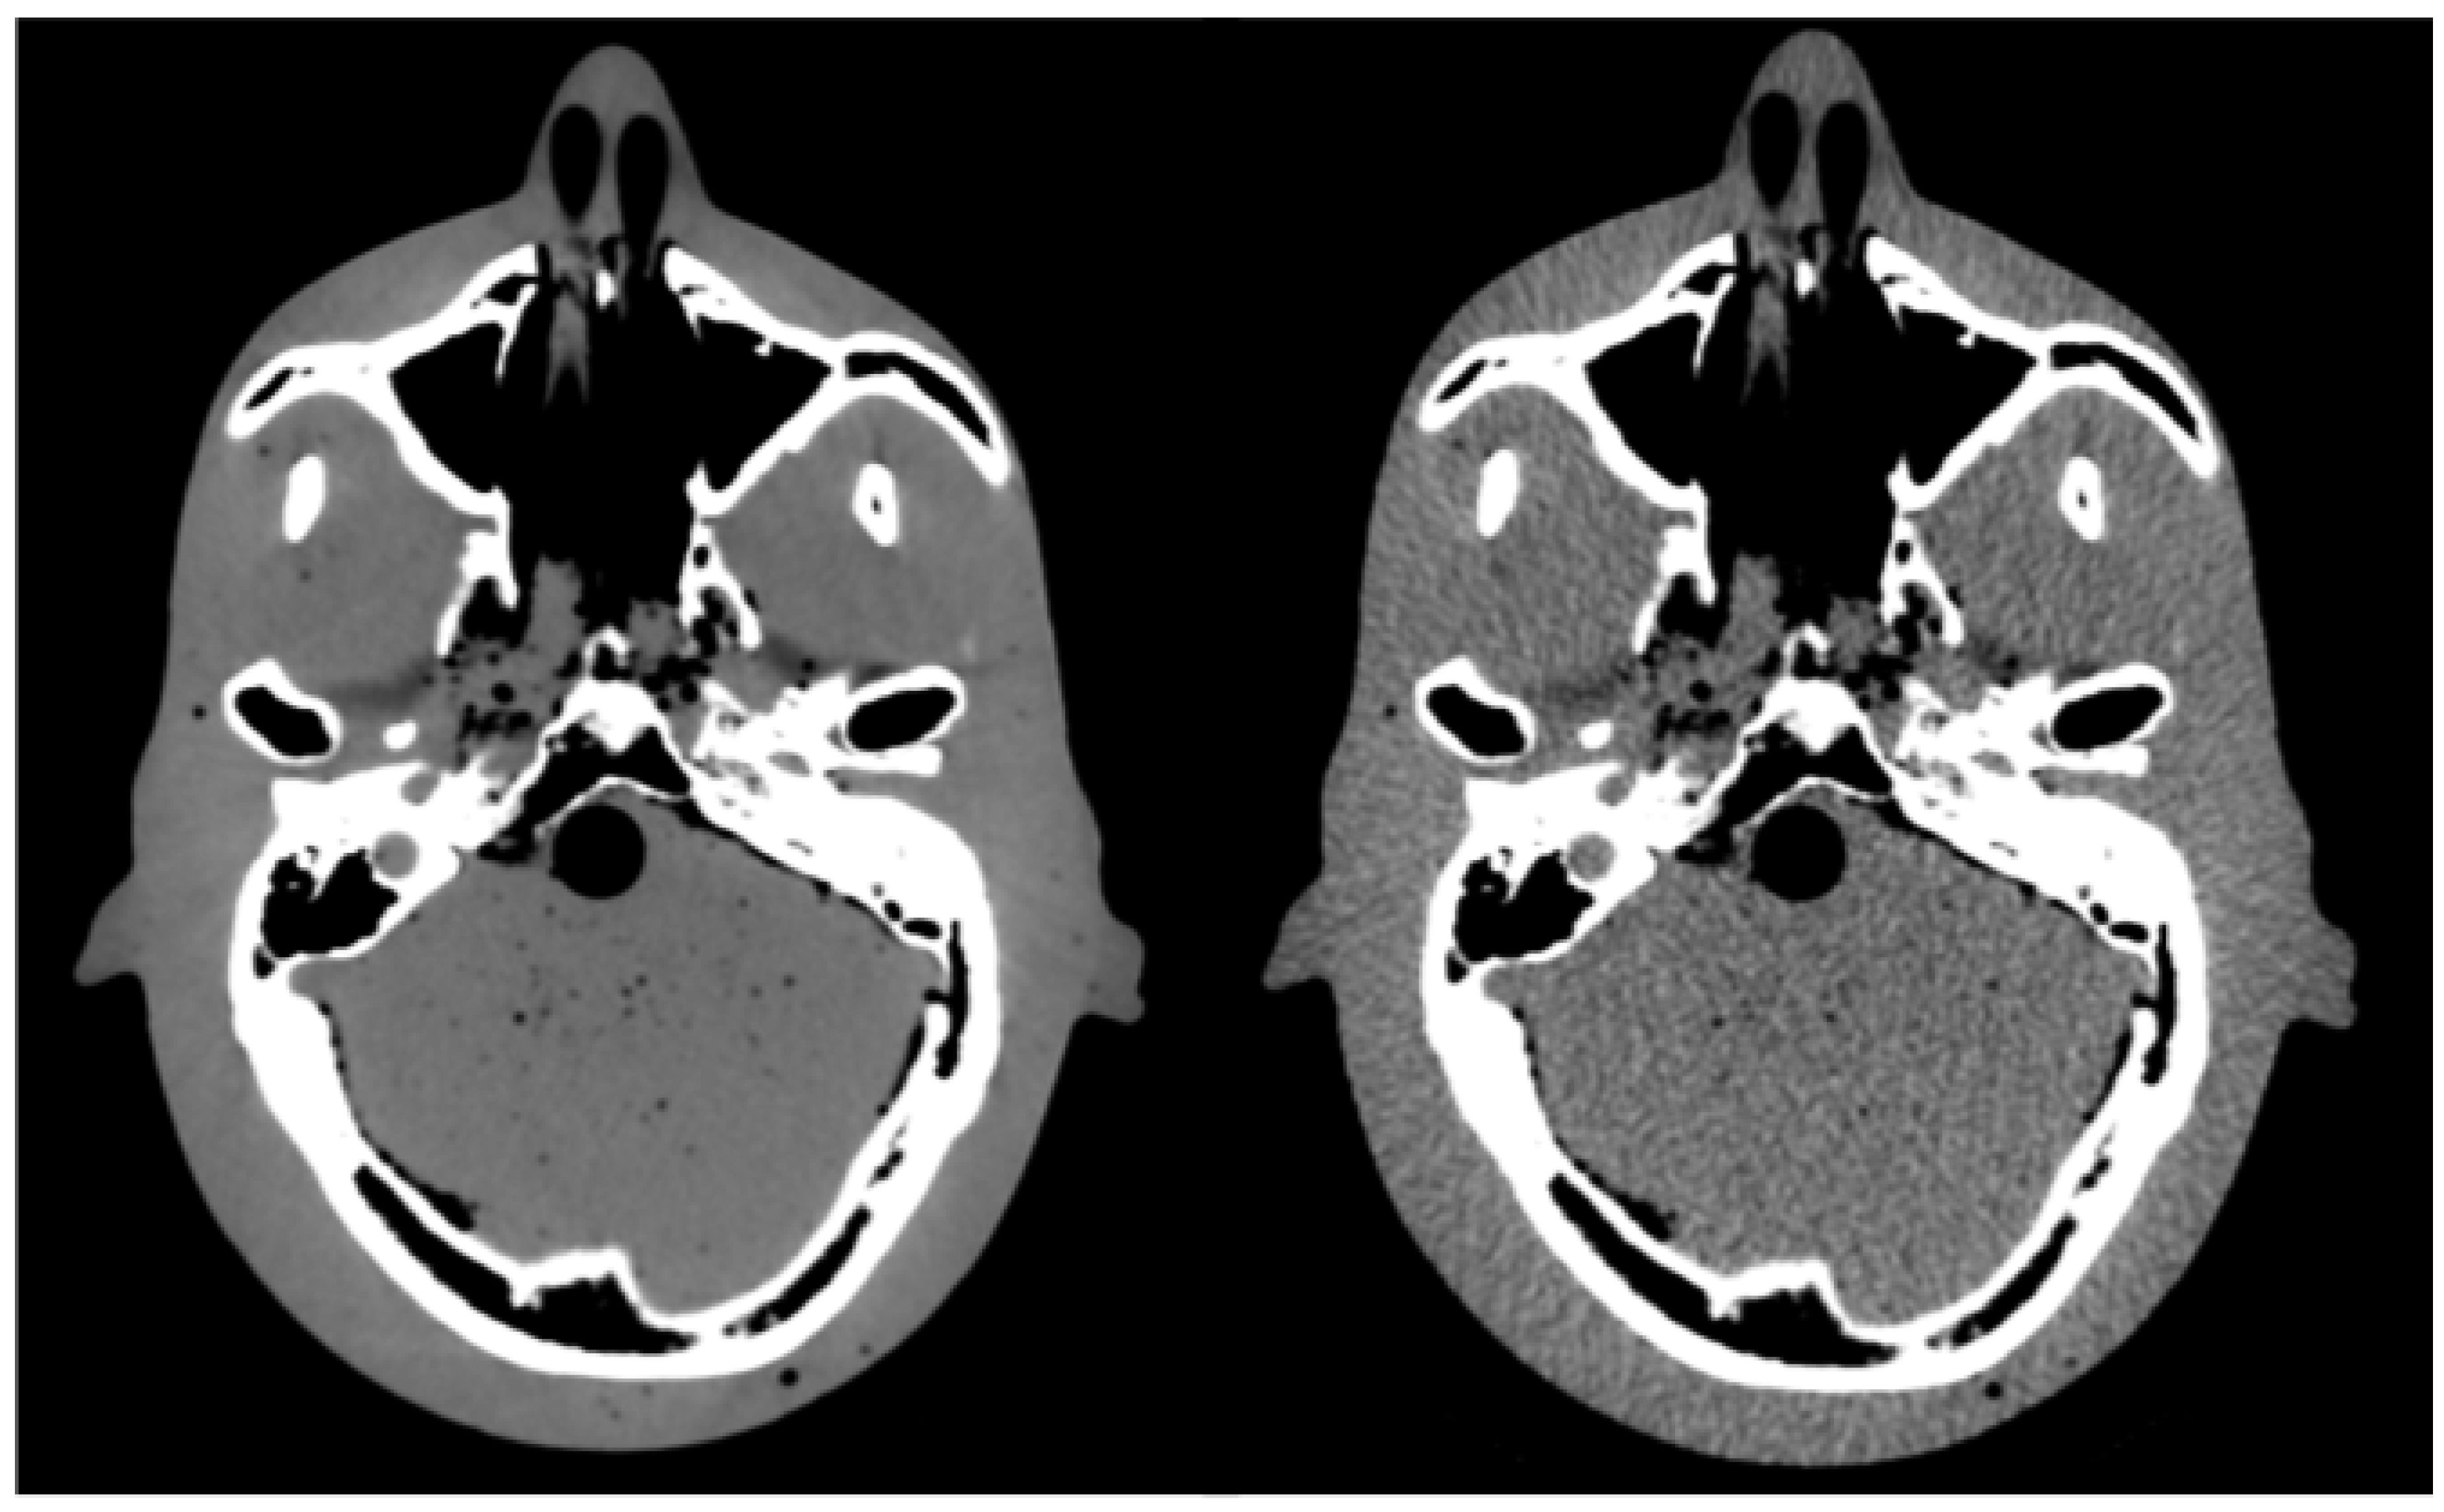

A pair of images (standard-protocol and corresponding low-dose) were analyzed for each of the six low-dose scanning protocols, as shown in Figure 2 for the lowest-dose protocol (CTDIvol = 4.2 mGy). The images were analyzed using SimpleITK—an open source interface to the image analysis toolkit Insight Toolkit (ITK) [20,21,22,23]. Due to the increased noise, each CT number in the standard-protocol CT image was represented by a distribution of CT numbers in the corresponding low-dose CT image. Therefore, voxels with the same CT number in the standard-protocol CT image had a range of different HU values in the low-dose CT image. We analyzed all the voxels in 11 central sagittal slices (the central slice corresponding to the middle of the phantom and 5 slices in each lateral direction from the central slice) so that most CT numbers occurring in the standard CT image were included in the analysis while optimizing the computation time. An example is shown in Figure 3a for the lowest-dose protocol, where a CT number of 0 HU in the standard-protocol CT image corresponds to a distribution with a mean value of −0.45 HU and a standard deviation of 20 HU. Based on the obtained distributions, the noise can be assumed Gaussian, which is demonstrated in Figure 3a with the best fit of a Gaussian function to the histogram (least-square method). For each CT number in the reference standard-protocol CT, we calculated mean value and standard deviation of the CT numbers in the corresponding voxels of the low-dose image. A lookup table that mapped original CT numbers to the calculated mean and standard deviation of the corresponding distribution was composed. Calculating the mean and standard deviation of the sample to estimate the parameters μ and σ of the distribution was found more reliable than fitting a Gaussian function to each histogram. Least-square fitting is sensitive to histogram binning, which would have to be carefully chosen for each distribution, as the number of entries in the histogram depends on how frequently a given CT number occurs in the reference image. Figure 3b shows the dependency of the standard deviation on the tube current for a CT number of 0 HU. The tube current is expressed as the percentage of the maximum tube current of 400 mA (standard protocol). The dependency is consistent with the Poisson distribution, as the number of photons is proportional to the tube current, and the lower number of events, the higher uncertainty on the CT number.

Figure 2.

Pair of CT images of head phantom: standard protocol (left) and low-dose protocol (right).